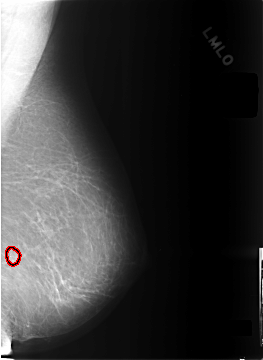

C_0301_1.LEFT_MLO

LEFT_MLO LINES 5752 PIXELS_PER_LINE 4200 BITS_PER_PIXEL 12 RESOLUTION 50 OVERLAY

FILE: C_0301_1.LEFT_MLO.OVERLAY

TOTAL_ABNORMALITIES 1

ABNORMALITY 1

LESION_TYPE CALCIFICATION TYPE PLEOMORPHIC DISTRIBUTION CLUSTERED

ASSESSMENT 4

SUBTLETY 4

PATHOLOGY BENIGN

TOTAL_OUTLINES 1

BOUNDARY